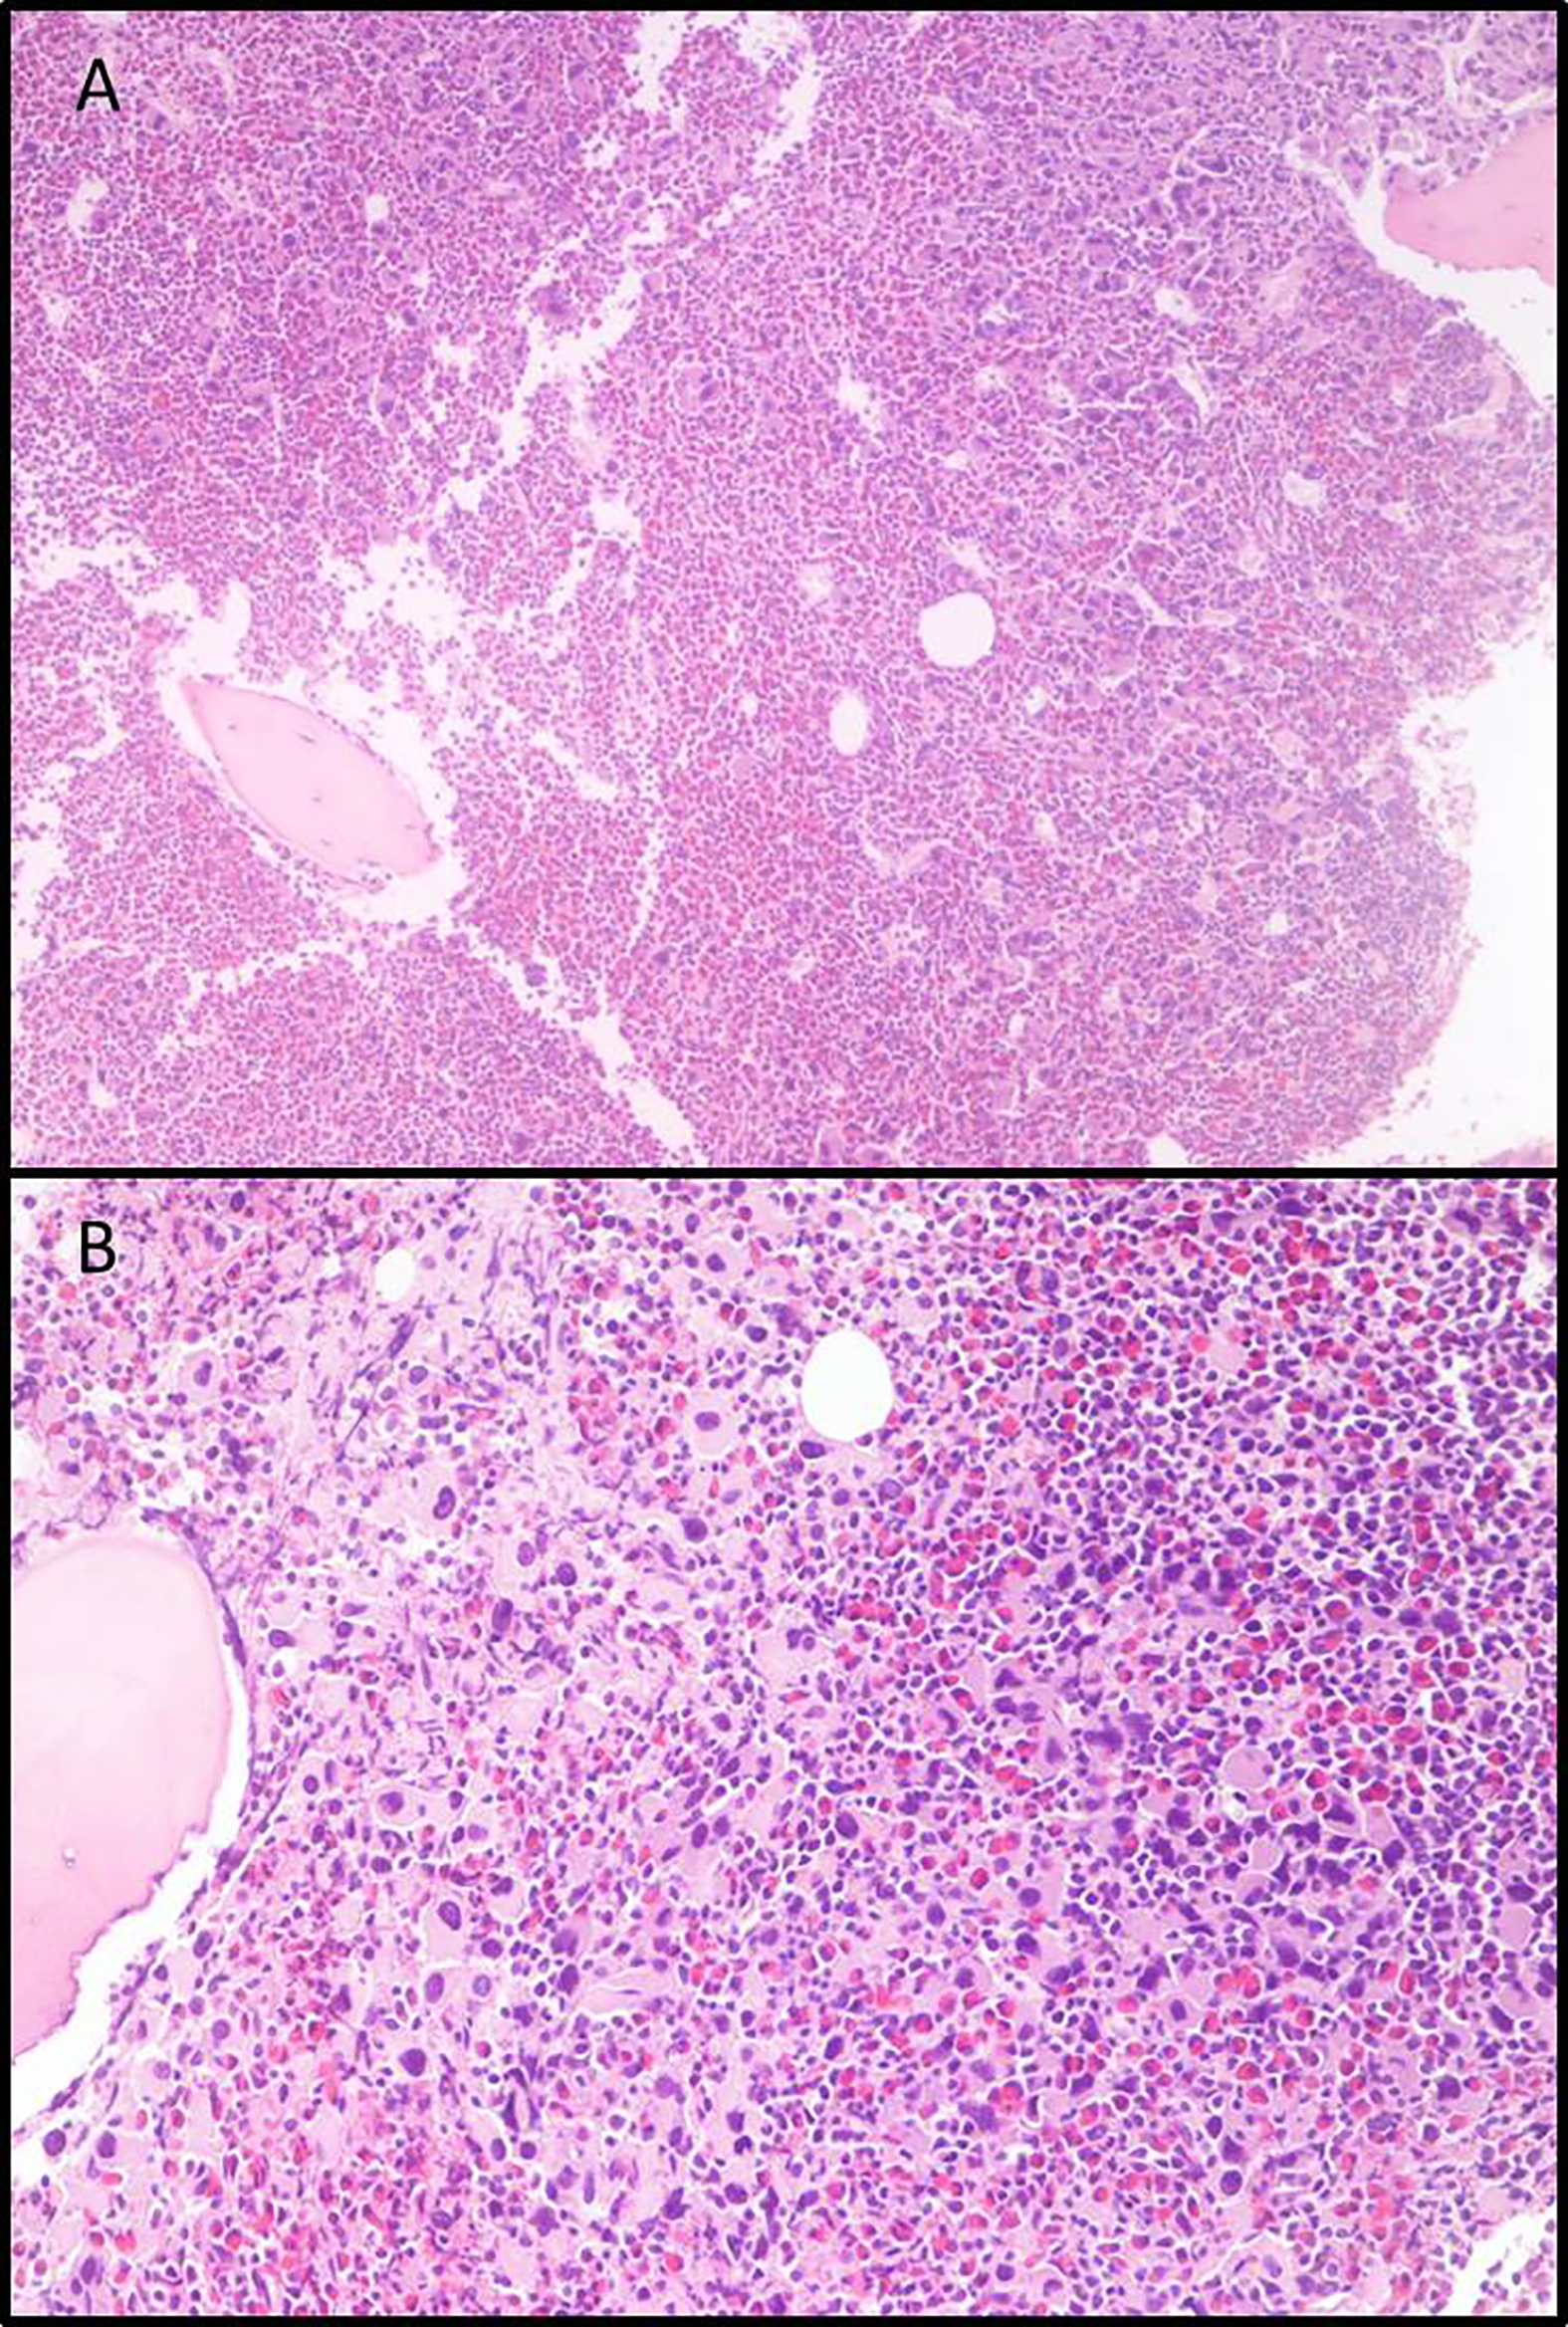

In June 2011, a 54-year-old woman was admitted to our Center, with leukocytosis, grade I anemia (Hb 11.4 g/dl), increased platelet count (3.903.000/µl), LDH 527 U/l, and Raynaud episodes mainly in her feet. Laboratory tests confirmed the increase in white blood cell count, up to 22.540 mcg/l, with neutrophils 36%, lymphocytes 14%, metamyelocytes 3%, eosinophils 7%, basophils 33%, blasts 7%, myelocytes 2%, and erythroblasts 2%. All other laboratory tests were in range. The molecular analysis of JAK2 did not reveal any mutation, whereas BCR-ABL1 was positive for the transcript “b2a2”. Bone marrow biopsy revealed large megakaryocyte conglomerates with abnormal elements (Figure 1); elevated blasts count (>20%) in repeated peripheral blood samples was also found, leading to the diagnosis of CML in accelerated phase according to ELN classification. Cytogenetic evaluation showed the standard BCL-ABL1 translocation 9/22, without any additional alteration. Sokal risk score (151.73) and Hasford risk score (2589.19) were elevated.

Figure 1

Bone marrow biopsies. (A) Eosinophilia and micro-megakaryocyte proliferation. Evident signs of fibrosis, original magnification 5×; (B) Micro-megakaryocytes characterized by hypo-lobated nuclei, original magnification 20×.